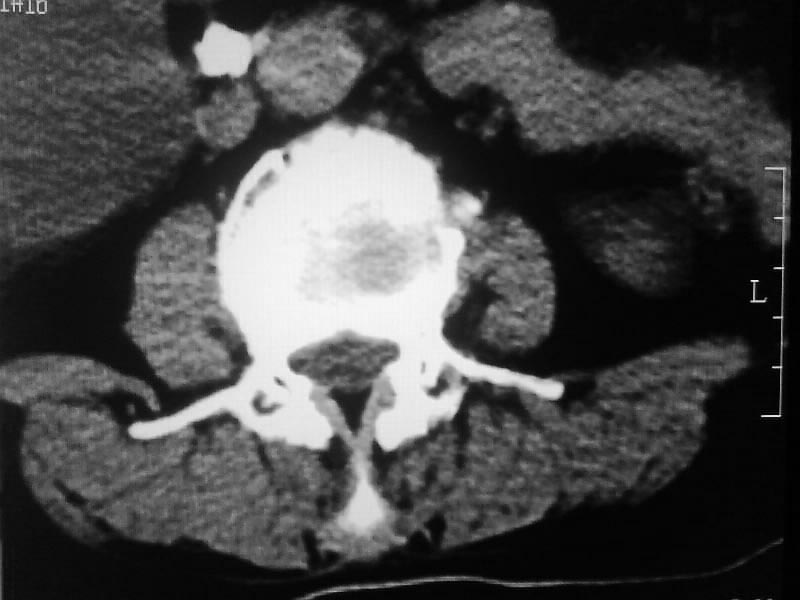

定位相示l2呈楔形改变(ct示陈旧性骨折改变,图像未传),l4.5椎体融合,以下是l4.5ct平扫.请各位看看,

考虑结核(有破坏、硬化及死骨)。

1、三四椎体结核,2、水平骶椎。

1、l1压缩性骨折(陈旧性)。

2、l3、4椎体结核。

就是腰1压缩性骨折,腰3\\4椎体结核(融合),水平骶椎.

支持 l1椎体陈旧性压缩性骨折;l3、4椎体结核(融合);水平骶椎。